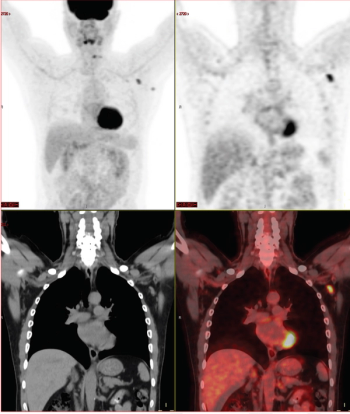

Adding 18F-FET PET to contrast-enhanced MRI can better determine which patients are responding well to immune checkpoint inhibitors or targeted therapies.